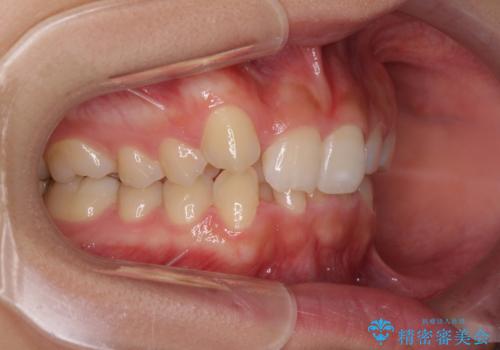

- 上顎の重なっている前歯を気にして来院された患者様です。

八重歯改善には抜歯が必要で、八重歯の移動量が多く、更には右側にずれている正中を改善する必要がありました。

インビザライン単体での治療は困難と判断し、補助装置により八重歯移動後にインビザラインを用いることとしました。